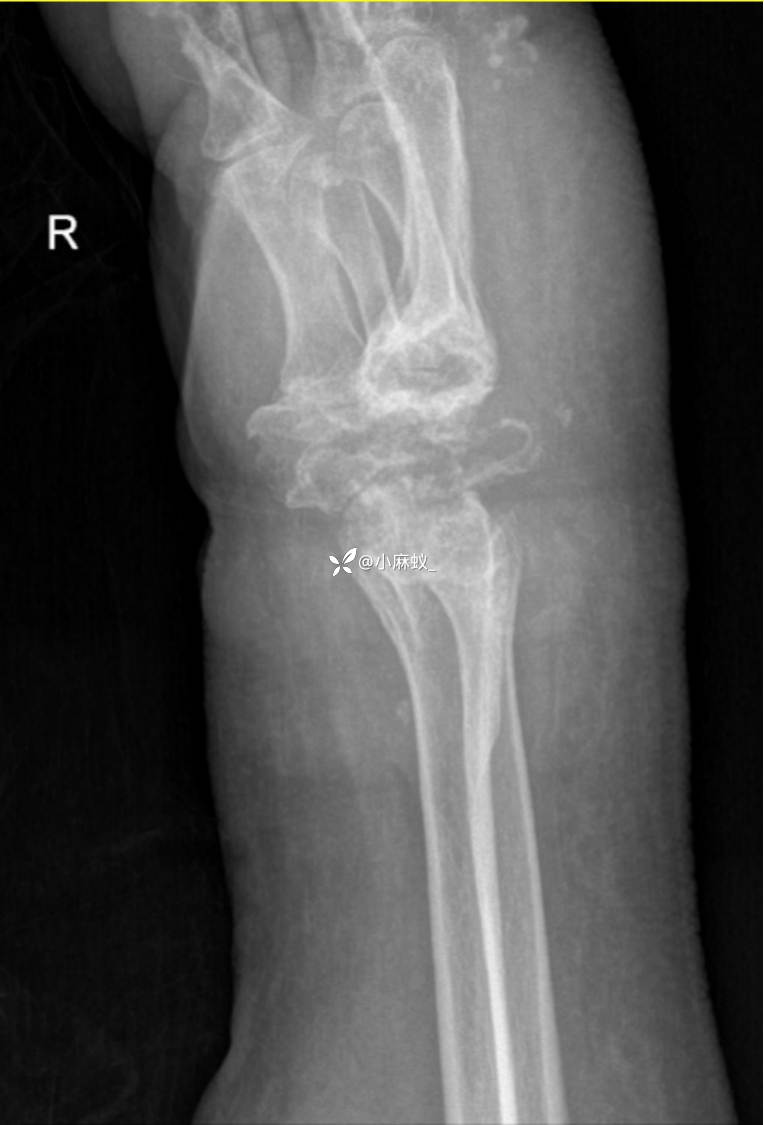

x线检查如下